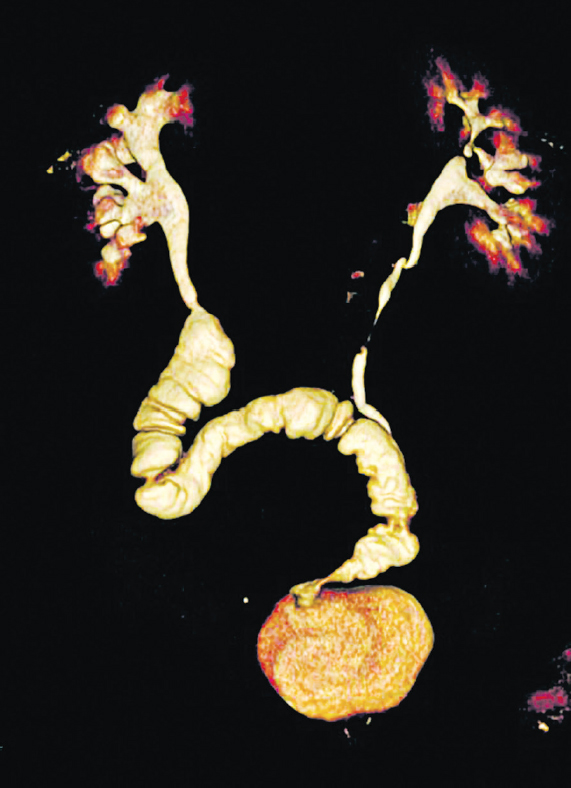

Fig. 11. Multisection computed tomography (MSCT) with contrasts of the patient 5 years after bilateral isoperistaltic 7-shaped ileoureteroplasty

Fig. 10. Bilateral isoperistaltic 7-shaped ileoureteroplasty

Bilateral small intestinal reconstruction of the ureters was performed in 40 (20.7%) patients. Most often, in 24 (60.0%) patients, U-shaped ileoureteroplasty was performed (Figs. 8 and 9), and more complex reconstructions were performed less often; that is, Y-shaped in 1 (2.5%) case, J-shaped in 3 (7.5%), L- and 7-shaped (Figs. 10 and 11) ileoureteroplasty in 6 (15.0%), and that with two separate ileografts in 6 (15.0%) cases.